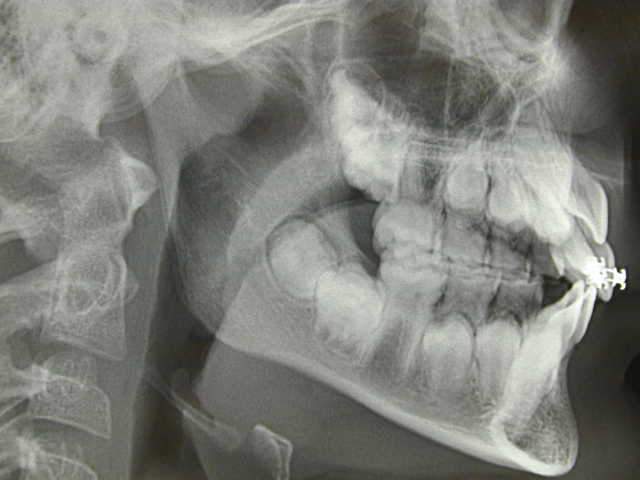

Lacand ayant des petits problemes de connexion internet, il m'a permis en son nom de diffuser les 3 images, qu'il vous commentera par la suite.